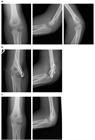

1. 非転位骨折(2mm未満):保存的治療(ギプス固定)と1週間後のフォローアップ。

1. 転位骨折(2mm以上):手術が推奨され、閉鎖整復やピン固定、または開放整復と内固定が行われる。

1. 固定方法:Kirschnerワイヤー(81.4%)が主流で、6週間後に除去。

1. 当院初診日の転位量が2.0mm以上であった6例は手術を行ったが、初診日までの外固定肢位は全例肘屈曲83°以下

1. 初診日の転位量が2.0mm未満であった17例は、前腕回内、肘屈曲96~120°で外固定し、全例骨癒合。可動域も良好。